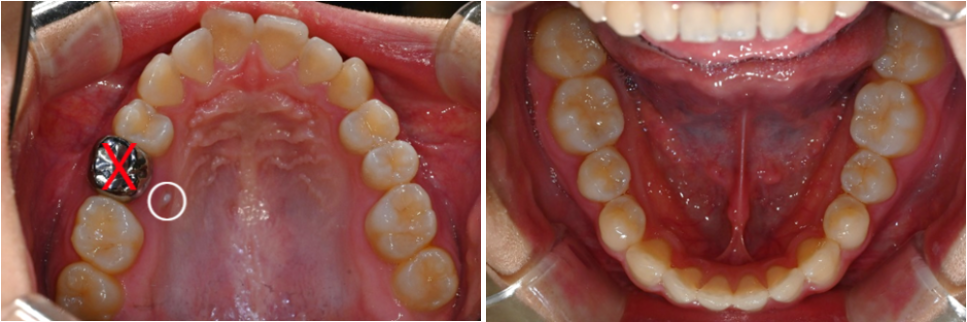

입천장 쪽으로 매복된 영구치의 일부가

관찰되었는데요.

유치 발치 후 매복된 영구치(# 15번)를

맹출 유도, 정상적인 배열을 도모하여

개방교합을 개선시키고

정상적인 어금니 교합을 만드는 것을

치료의 목표로 설정하였습니다.

23.06.11

부정교합을 맞추기 위해

2개의 상악 스크류 식립을 동반한

비발치 교정을 계획했으며,

교정 후 기존 안모 변화는 크지 않을 것으로 예상됩니다.

23.06.11 ~ 25.01.12

매복되어있던 작은 어금니가

잇몸 위로 조금씩 모습을 드러내던 과정입니다.